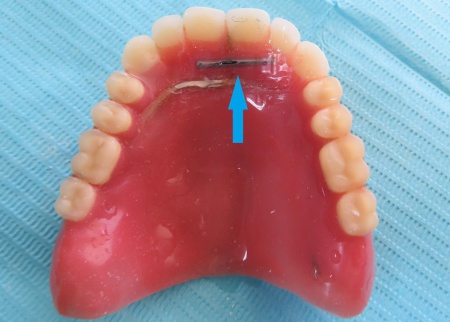

70代女性 ヒビが入った入れ歯に補強線を埋め込む修理をした症例

- 総入れ歯

- 治療回数の目安 1回

約2,000円

(保険診療2割負担)

・着脱式のため、食後の清掃が必要です ・最初のうちは異物感があり、慣れるまで時間がかかる場合があります ・慣れるまでは、入れ歯の裏側の粘膜に傷ができる場合があります...